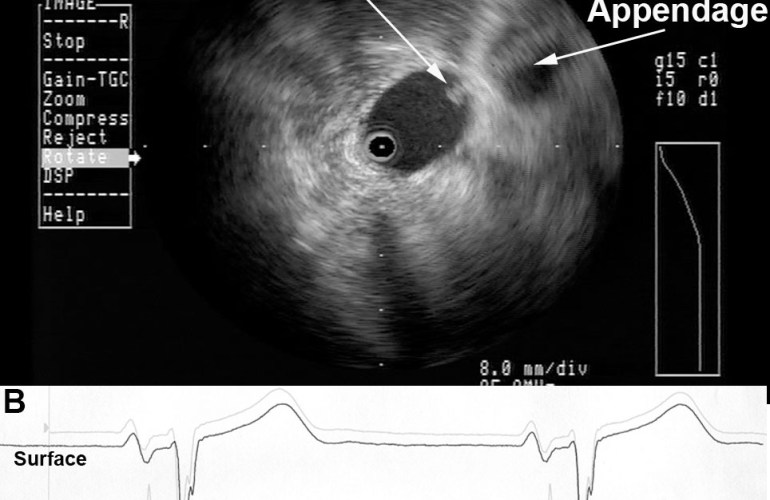

Radial ICE can be used to obtain especially informative electroanatomic correlations and has been described extensively during atrial fibrillation ablations. [1,2,3] Aside from guiding the localization of pulmonary vein potentials during intra left atrial ICE guided procedures (shown in Radial ICE for Left Atrial Procedures) there are several instances where radial ICE facilitated electroanatomic correlates can discern situations where ablation is not necessary during atrial fibrillation ablations. The left atrial appendage is often located quite close to the left superior pulmonary vein and left atrial appendage far-field electrograms can be confused with pulmonary vein potentials if this is not suspected based upon electroanatomic correlation. Figure 1A depicts the radial ICE catheter positioned in the left superior pulmonary vein (adjacent to the left atrial appendage) and 1B shows the intracardiac electrograms (EGM) recorded in the left upper PV (darker, smaller amplitude) and LAA (lighter, larger amplitude); The LUPV signal appears to be a low-pass filtered version of the LAA signal.

Figure 1 Left Atrial Appendage Electrogram Mimicking Left Upper PV Potential. Image A depicts the radial ICE catheter positioned in the left superior pulmonary vein and B shows the corresponding intracardiac electrogram (EGM) recorded in the left superior PV (darker, smaller amplitude). EGM’s from within the LUPV (darker) and LAA (lighter, larger amplitude) are superimposed.